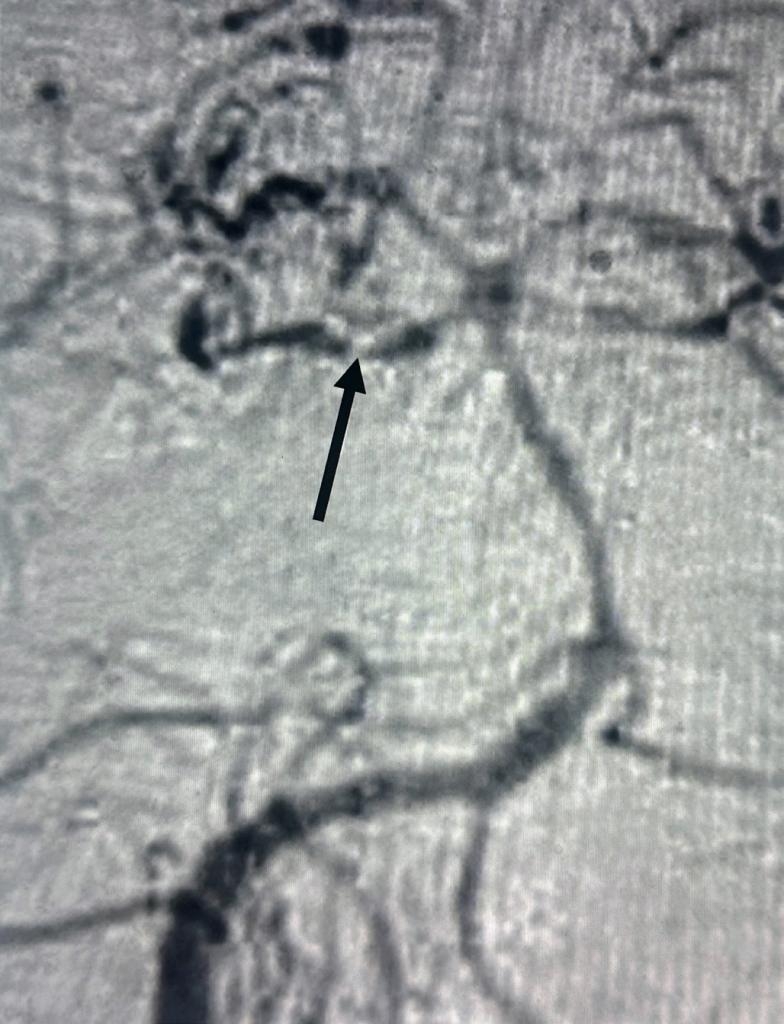

磁振造影血管攝影顯示小腦上血管痙攣(黑箭頭)。